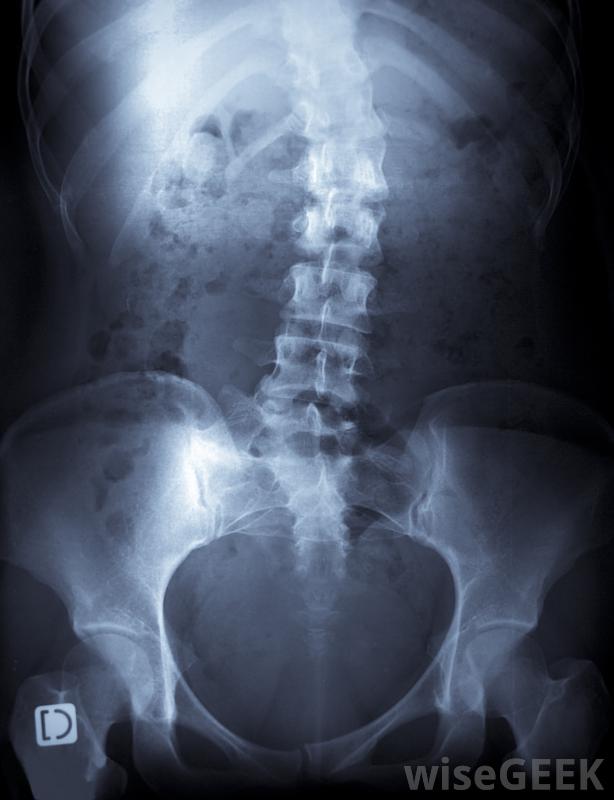

脊柱侧凸导致的脊柱弯曲的严重程度是决定最佳治疗的一个因素。

患者的身体症状,摸摸脊柱和周围组织,并拍背部x光片。为了做出正确的诊断,医生可能会进行额外的检查,以确定潜在原因。有些脊柱侧凸是先天性缺陷、神经肌肉疾病和关节炎所致不过,这种情况通常是特发性的,这意味着无法确定病因。